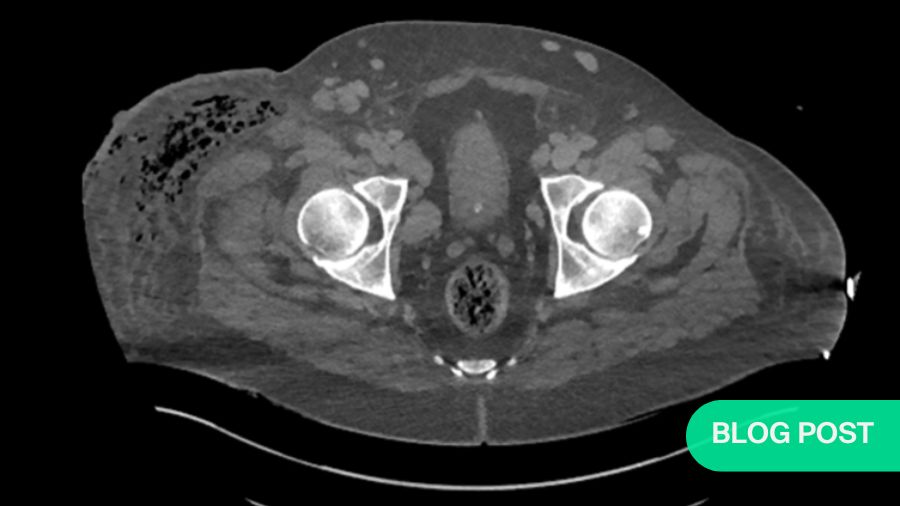

Turns out, I had not gotten ahead of the infection after all. Not even 24 hours after the amputation which I thought had cured her, every muscle in her thigh was necrotic. The infection was rampant, and moving proximally. The fascia was probably the worst affected tissue. Eventually, we had no choice but to progress onto a hip disarticulation amputation. Mind you, there was never any bone involved at all. The infection strictly affected the soft tissue.